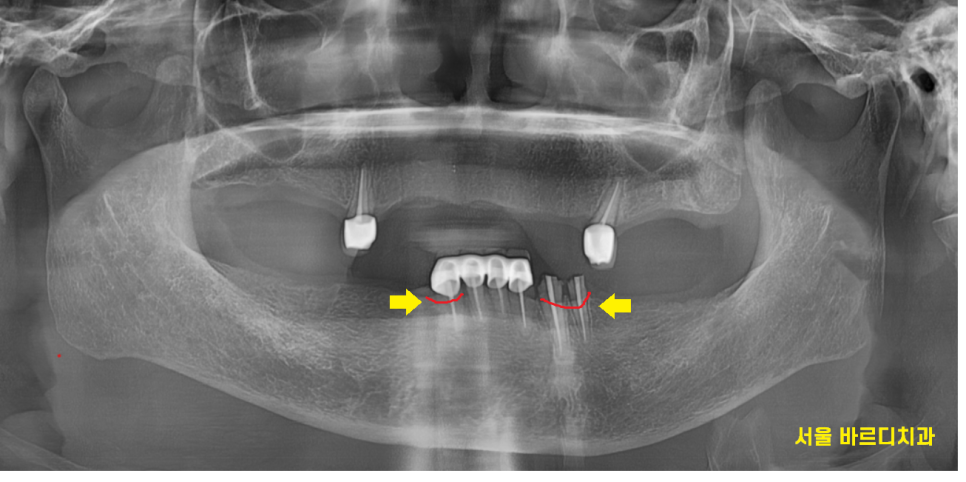

보험 임플란트를 사용하여

수술하기로 계획해드리고

240125

틀니 사용중 치아 부러짐

문제의 치아 깨끗하게 발치한뒤

임플란트 2개를 식립해드렸습니다.